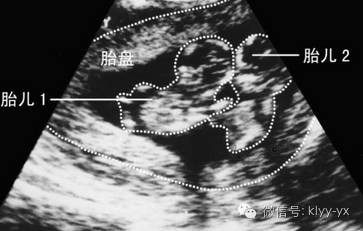

4、二胎存在问题,如胎儿宫内缺氧、多胎妊娠、宫内感染、胎儿过大等。